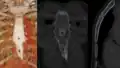

This variation is usually present at the lower one-third of the sternal body. It has an oval shape and a unique "bow tie" appearance when seen on axial computed tomography. The diameter of the sternal foramen ranges from 6 to 16 mm with an average diameter of 6.5 mm.[2] Sometimes, the foramen can be present at the xiphod process. In extremely rare cases, the foramen is found at the manubrium.[3]

Sternal foramen on axial and sagittal CT. The "bow tie" appearance is seen on the axial view.

Sternal foramen on axial and sagittal CT. The "bow tie" appearance is seen on the axial view. -